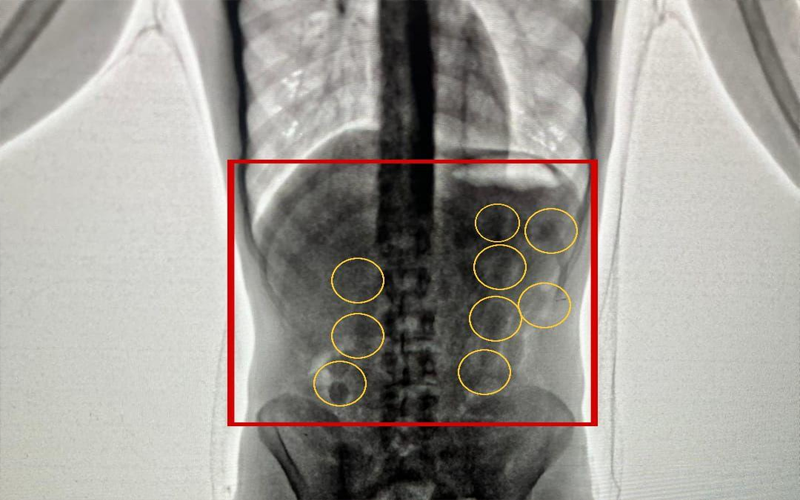

نيسان ـ بين الناطق الاعلامي باسم مديرية الأمن العام أن كوادر إدارة مكافحة المخدرات أحبطت في مطار الملكة علياء الدولي محاولة تهريب 2 كغم من مادة الكوكايين المخدرة داخل أحشاء شخصين من جنسية أجنبية.

وبعد تفتيشهما والكشف عليهما بواسطة الاجهزة اللازمة اكتُشف وجود كميات من المواد المخدرة داخل أحشائهما ، وجرى إخراج هذه المواد بالطرق الطبية، وقُدرت ب 2 كغم من مادة الكوكايين المخدرة .